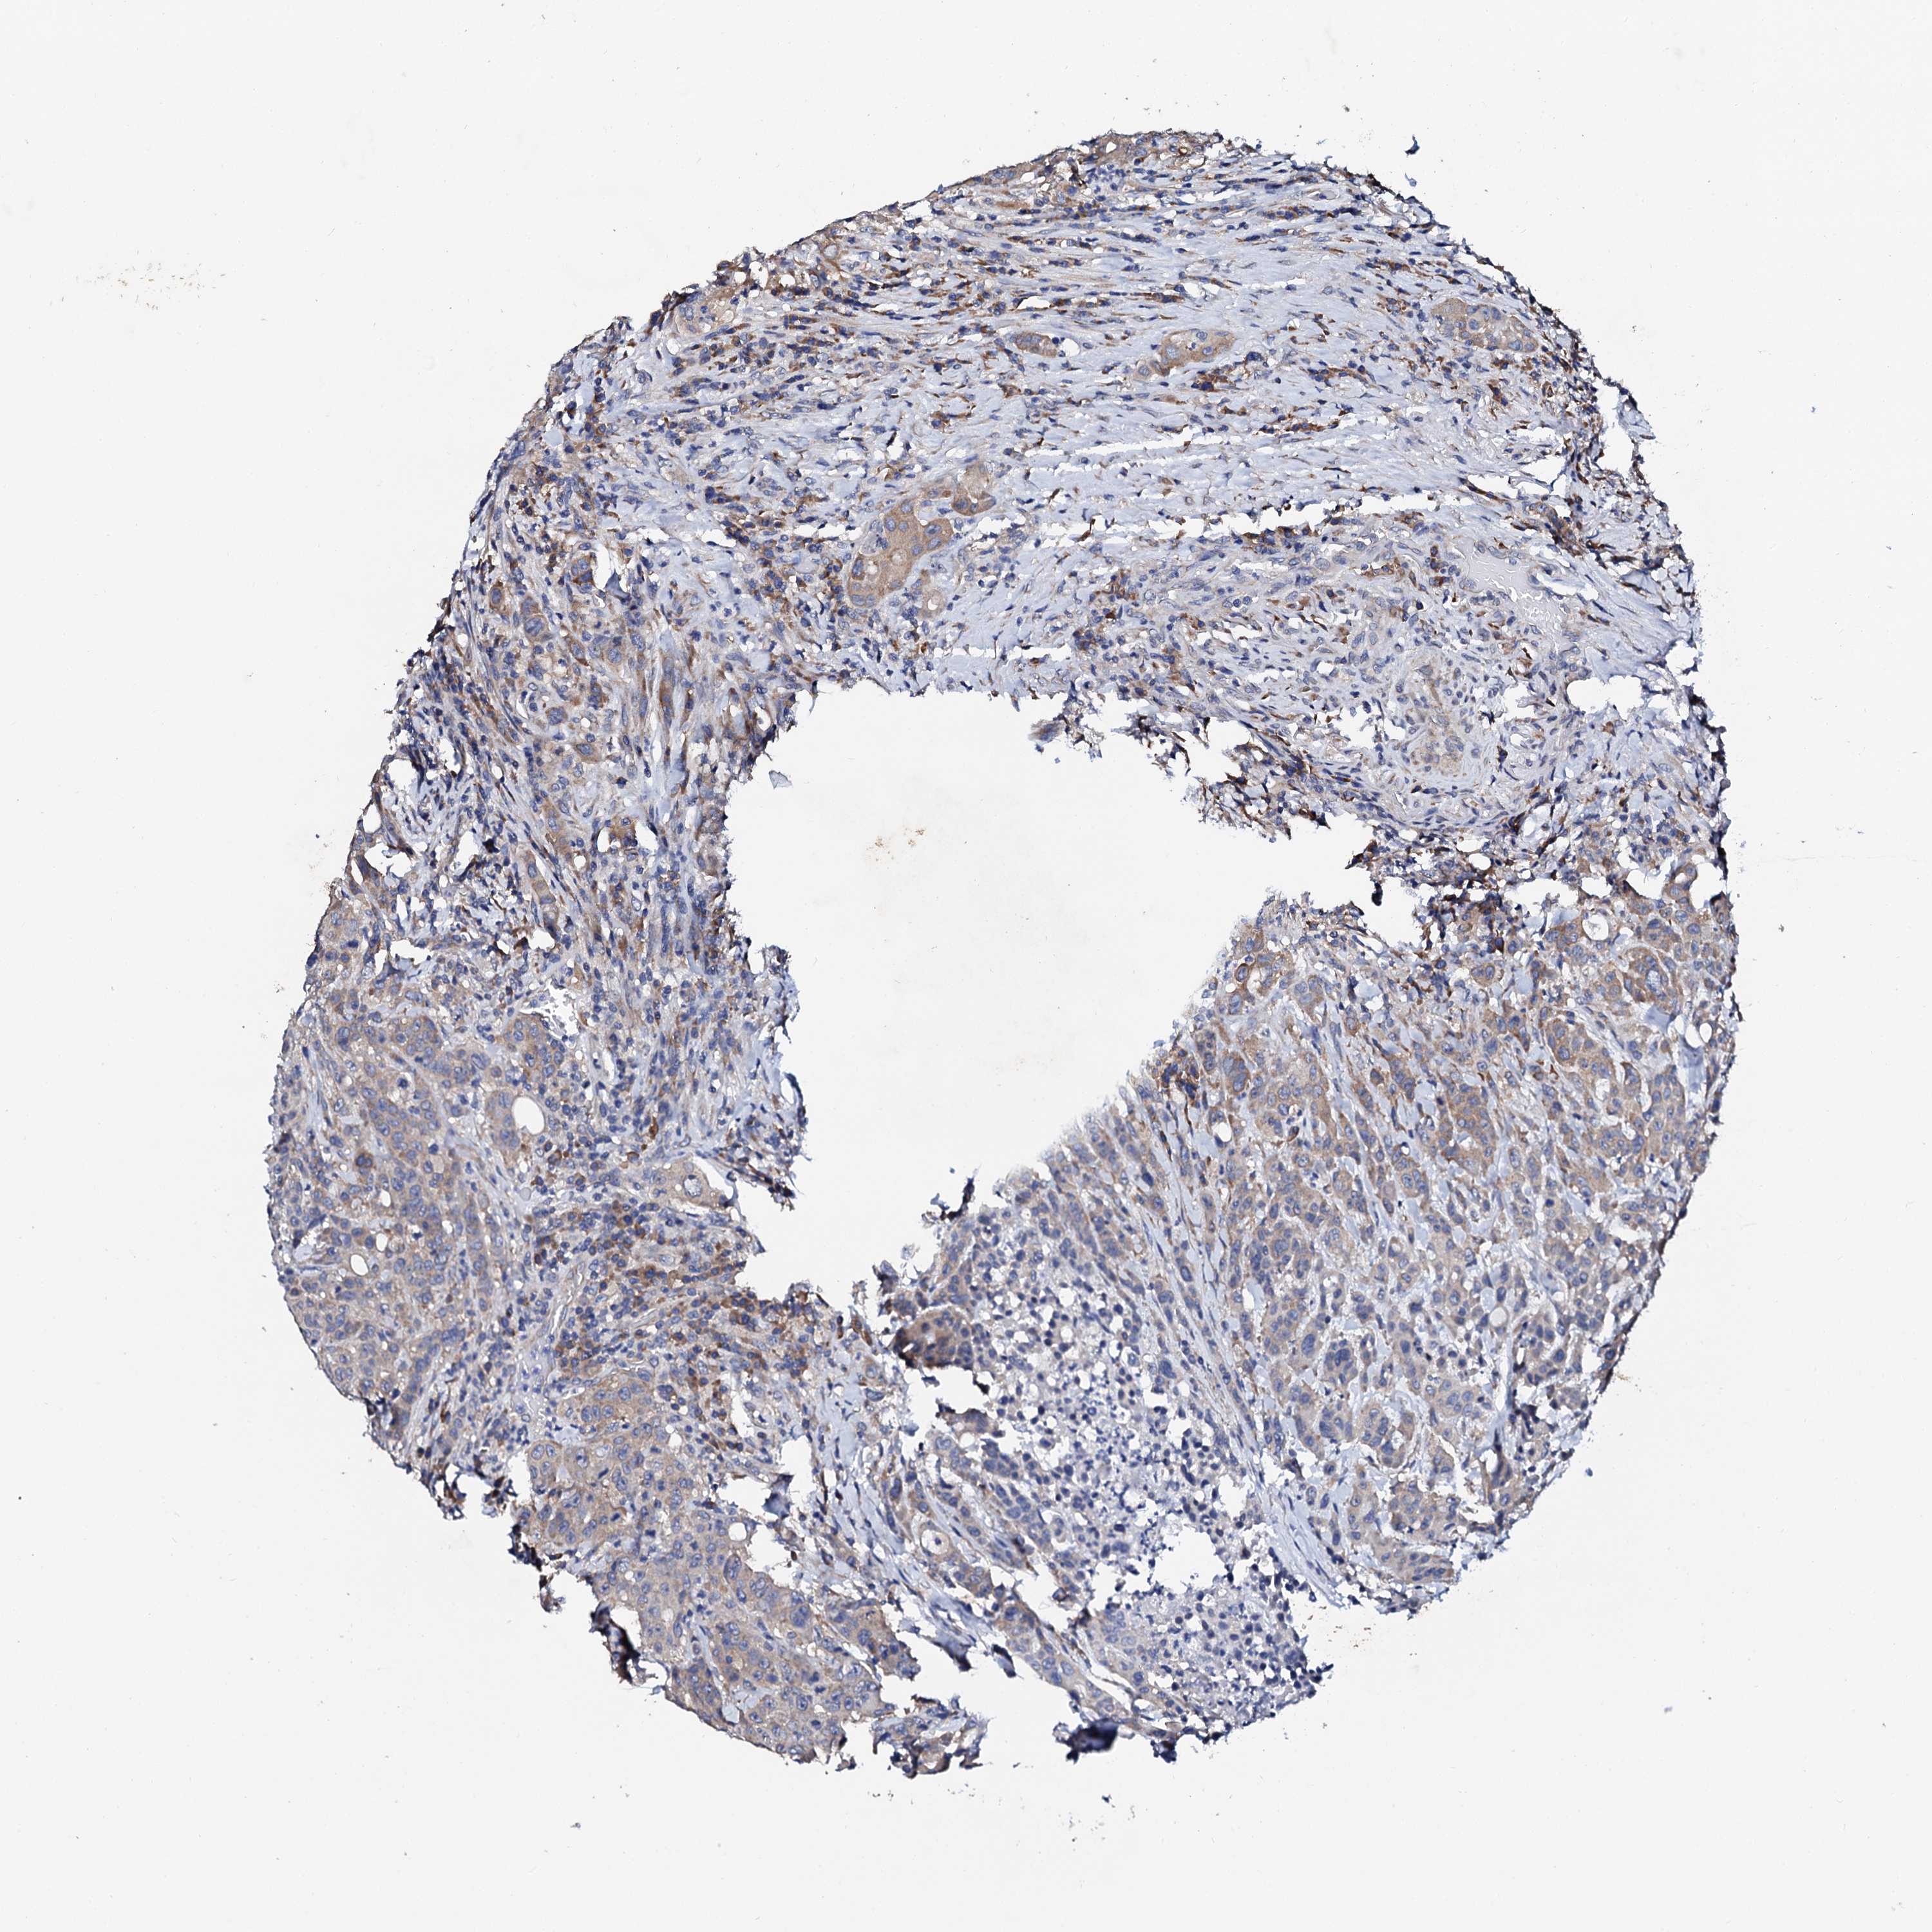

CANCER COLORECTAL CANCER Show tissue menu

Colorectal cancer

Rectum adenocarcinoma

NUP58 is not prognostic in Rectum Adenocarcinoma (TCGA)